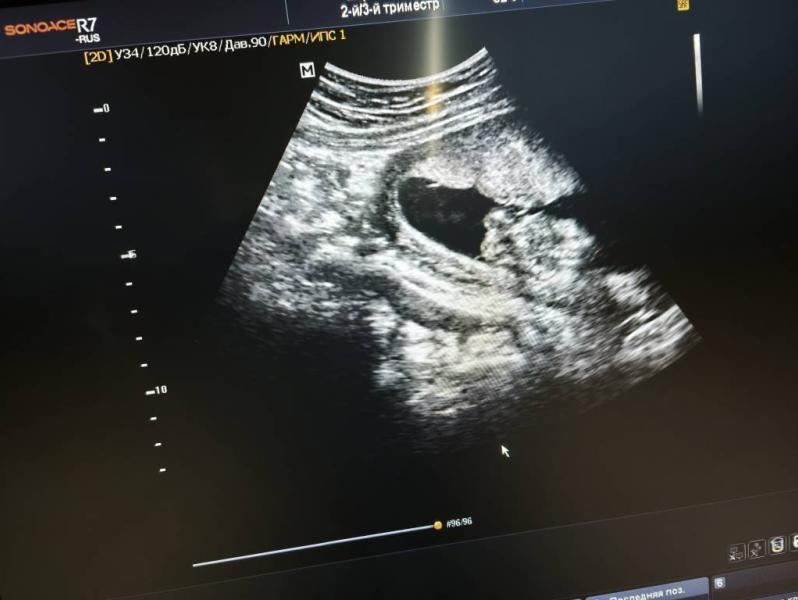

Девочка) вижу зачатки изображения кофейного зёрнышка

Тут на фото не понятно ничего

Он крутил, вертел датчик. Я успела попу сфоткать. Но там ничего не торчало совсем.

Я даже не пойму где смотреть 😅